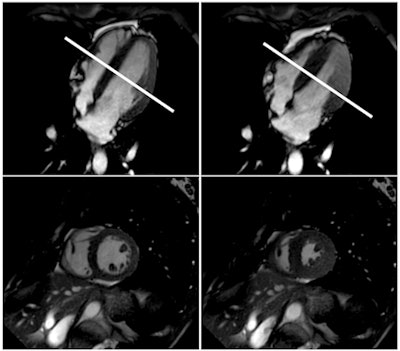

The subjects underwent a 1.5-tesla cardiac MRI to assess left-ventricular end-diastolic volume, end-systolic volume, ejection fraction, fractional shortening, and other measures. A second MRI scan was performed to measure blood flow in both common carotid arteries using phase contrast imaging.

The MRI exams allowed the researchers to observe the cardiovascular changes involved in the diving reflex in real-time. During apnea, the amount of blood flowing to the brain through the carotid arteries increased and then leveled off.

At the beginning of the breath-hold period, the heart pumped more strongly than when the heart was at rest, the researchers found. Over time, the heart dilated and began to struggle, and by the end of the apnea period, the divers' heart function began to fail.

At that end point, not enough blood is being pumped to the brain, Dörner explained, and the heart is unable to pump against the high resistance of the blood vessels.

And while the changes in the divers' systolic heart function during apnea are similar to patients with systolic heart failure, the major finding is that the divers' heart function recovered within minutes of breathing again. This suggests that the elite free divers develop mechanisms that help them adapt to the cardiovascular changes that occur during apnea.